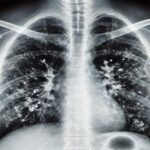

Prof. Dr. Şener, viral enfeksiyonlardaki artışa dikkat çekti. Gribal enfeksiyonlar kapsamında influenza vakalarının ciddi bir artış gösterdiğini belirten Şener, “Influenza dışındaki RSV ve rinovirüs vakaları da tespit ediliyor. Gribal enfeksiyon sonrası bakteriyel enfeksiyonlar süperenfeksiyon olarak gelişebilir ve bu durum zatürre, pnömoni gibi hastaneye yatışı gerektiren vakalara yol açabilir. Aile hekimleri aracılığıyla grip aşısı olmayı ihmal etmemek lazım” dedi.

65 yaş ve üstündeki bireyler için özel bir uyarıda bulunan Prof. Dr. Şener, “Bu yaş grubunda RSV enfeksiyonu büyük önem taşıyor. RSV, akciğerde ciddi iltihaplanmalara yol açabiliyor ve bunun aşısı mevcut. Özellikle 75 yaş üzerindeki bireylerin aşı yaptırması hayati önem taşıyor. 65 yaş üzerindeki bireyler için viral enfeksiyonlar daha ağır seyredebiliyor. Koronavirüs pandemisi ile birlikte bu tür enfeksiyonların etkilerine alıştık; pandemiden sonraki süreçte de benzer ağır viral tablolara rastlamaya başladık. Ciddi solunum yetmezliği, ateş ve titreme gibi semptomların ortaya çıkmasıyla hastaneye başvurular artıyor. Bu hastalar bazen yoğun bakıma alınmak zorunda kalabiliyor” şeklinde konuştu.

Hafif şekilde hastalığı geçirenler için de uyarılarda bulunan Prof. Dr. Şener, “Hafif geçiren bireylerde dahi akciğer hasarları ilerleyen dönemlerde KOAH ve astım gibi rahatsızlıklara yol açabiliyor. Uzun süreli ilaç kullanma gerekliliği doğuyor. Kalp hastalığı, hipertansiyon ve diyabeti olan bireylerde ise daha ağır klinik tablolar gözlemleniyor. Viral enfeksiyonu hastanede atlattıktan sonra öksürük ve balgam gibi belirtiler devam edebilir. Bu durumda zatürre gelişebilir ve antibiyotik tedavisi şarttır. 65 yaş üstü bireyler, hafif bir gribal enfeksiyon geçirdikten sonra öksürük ve balgam yaşarlarsa, mutlaka uzman bir doktora görünmelidirler. Zatürre olabilirsiniz ve bunun için gerekli tetkikler yaptırılmalıdır” dedi.

Prof. Dr. Şener, zatürre aşısının önemini ekleyerek, “Zatürre aşısı, yaşamınız boyunca bir kez yapıldığında zatürre vakalarının yüzde 90’ını önleyebilir. Özellikle 65 yaş üzerindeki bireylerin aşı yaptırması önemli. Grip aşısı gibi değil, zatürre aşısını sadece bir kez yaptırdığınızda uzun süre koruyuculuk sağlıyor. Solunum yolu enfeksiyonlarında, polikliniğimde yüzde 20’lik bir artış gerçekleşti. Havaların soğumasıyla aşı için zaman bulunmaktadır. Aşı olunduğunda hastalanma riski azalır” şeklinde sözlerini tamamladı.